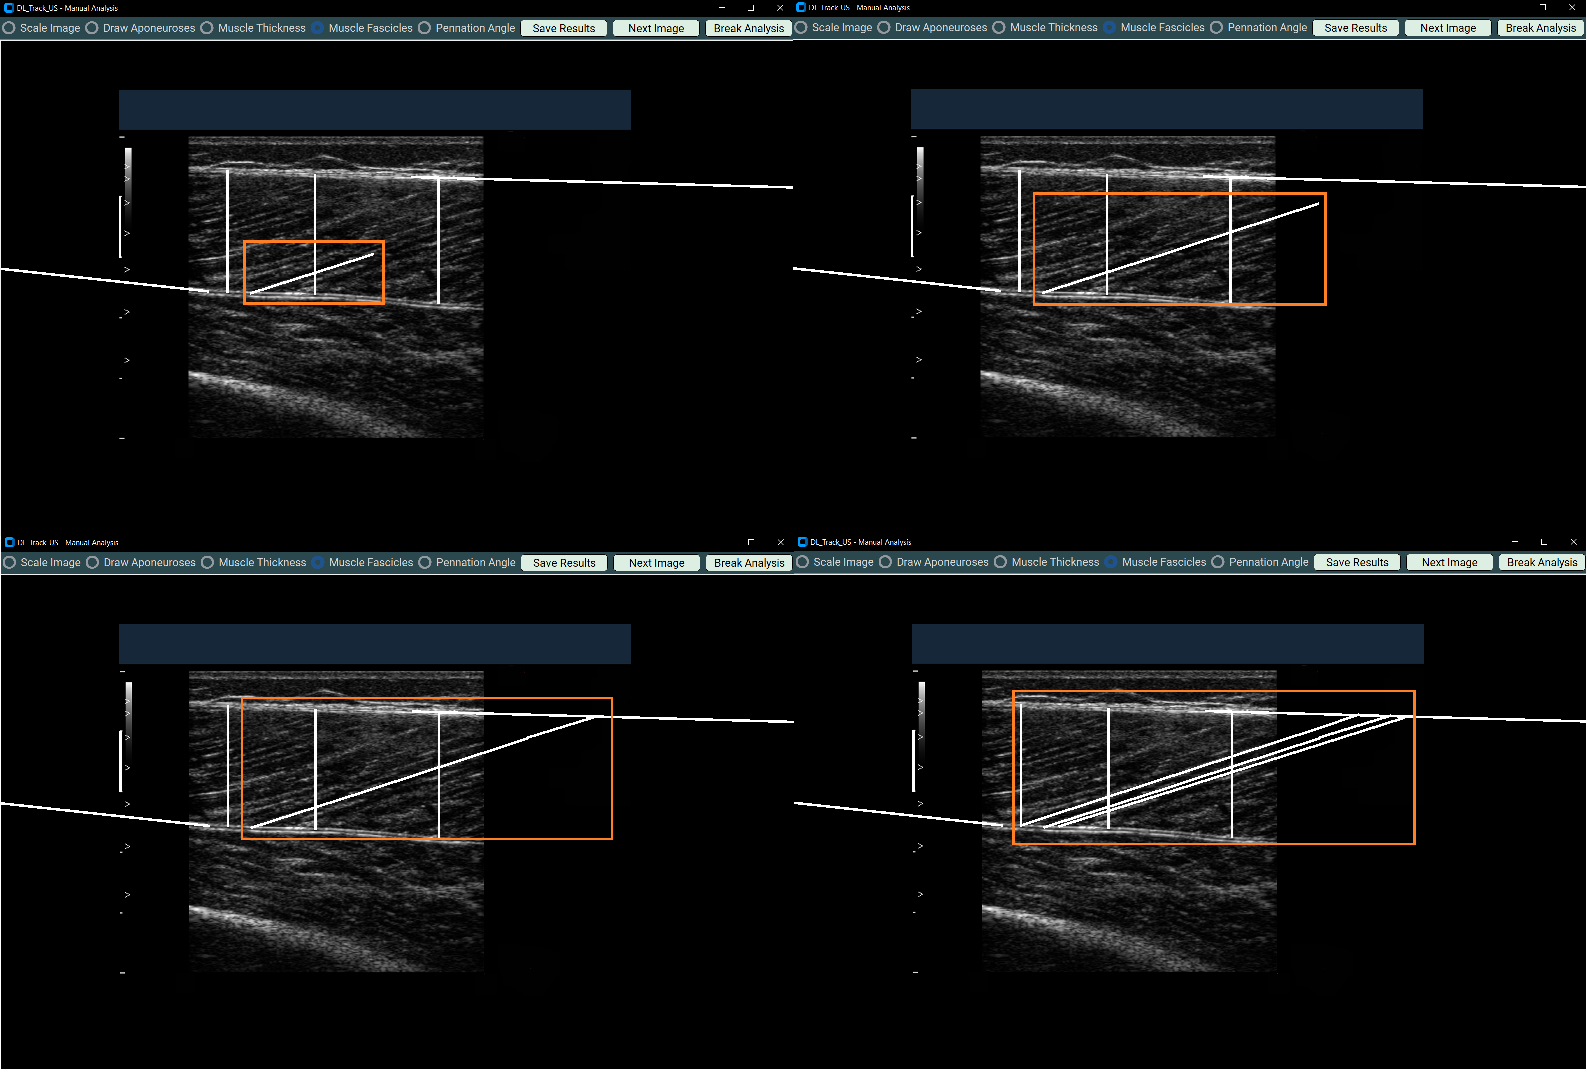

4.4 Drawing Fascicles¶

- Select Muscle Fascicles.

- Draw at least three fascicles in different regions.

- Each fascicle must have three segments:

- Each segment must start where the previous segment ended.

- Avoid extra mouse clicks.